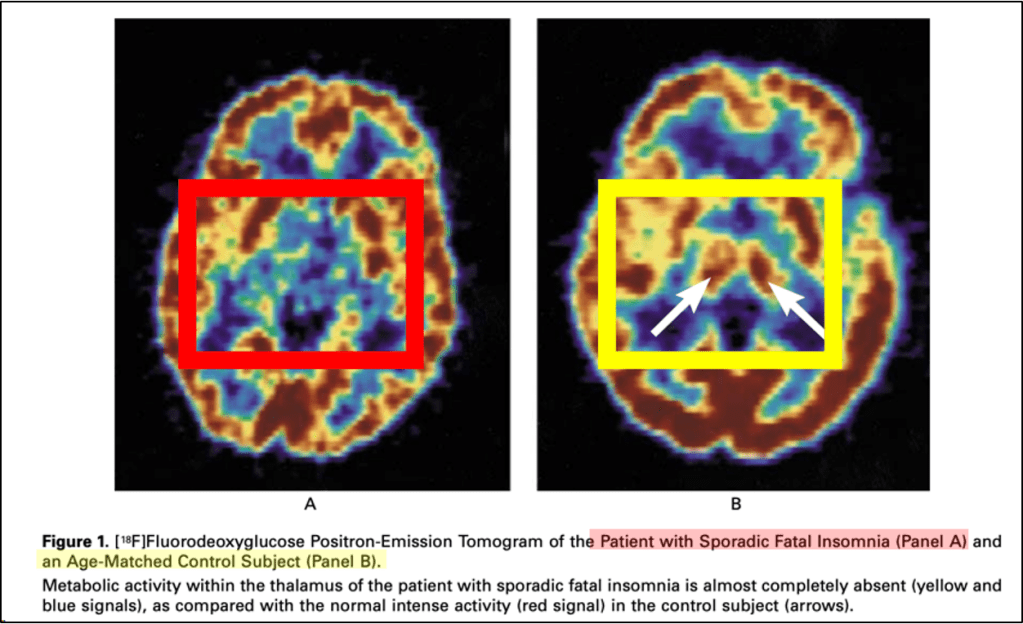

So, why are people with FFI unable to sleep? This actually has to do with the location of where these abnormal prion proteins are forming. As noted earlier, in the 1986 case report, the authors found thalamic degeneration at autopsy. This anatomic pattern has been confirmed with subsequent case series as well, with the consistent finding that familial fatal insomnia is ultimately a thalamic disorder. Below is a PET scan example from the brain of someone with FFI. There is no metabolism in the thalamus; that part of the brain shuts down.

Since the thalamus is a primary regulator of the sleep-wake cycle, from wakefulness to non-REM to REM sleep, its localization is reasonable. The thalamus is hyperconnected to the rest of the brain, like an old-school phone switchboard operator, and one of the many things it regulates is sleep. It is not fully understood why the thalamus is uniquely susceptible in individuals with a PRNP gene mutation, compared with other brain regions that carry the same mutation. There’s two plausible mechanistic theories that we can briefly review. The first was that there might be specific receptors for these abnormal prions that are present only in the thalamus. One proposed candidate is the limbic associated membrane protein or LAMP, which is a type of cell membrane receptor that only exists on neurons in parts of the brain within or closely associated with the thalamus. Another theory is that different degrees of prion glycosylation inside the thalamus could affect how these prions function.